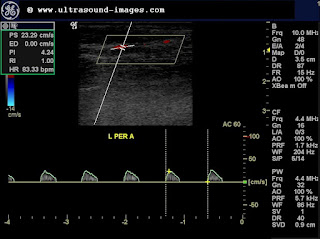

The colour Doppler ultrasound images below show changes after treatment with anticoagulants:

Note the sharp augmentation of flow on calf pressure. These images were taken four days after treatment with anticoagulants. Obviously the thrombosis of the veins has more or less resolved. the right anterior tibial vein also shows some measure of flow ( see image below):